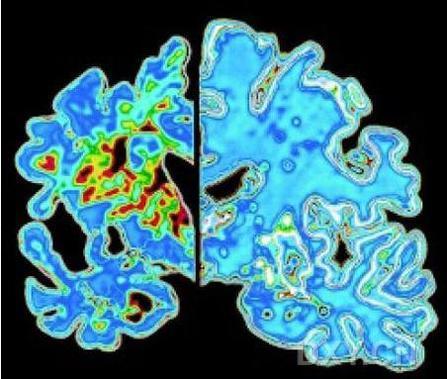

在新实验中,研究人员给经过遗传工程设计而患有阿尔茨海默氏症样疾病的小鼠服用蓓萨罗丁。72小时内,小鼠脑内沉积的β淀粉状蛋白半数被清除,最终的总清除率达到75%。蓓萨罗丁似乎促使小鼠大脑中的免疫细胞“吃掉”或吞噬积聚的淀粉状蛋白。医学界普遍认为,阿尔茨海默氏症患者记忆能力损伤主要由可溶性淀粉状蛋白导致,而服用蓓萨罗丁6小时后,患病小鼠脑内的可溶性淀粉状蛋白水平下降25%。这些小鼠的认知、社交及嗅觉能力均有所改善。

Alzheimer's disease is associated with impaired clearance of β-amyloid from the brain, a process normally facilitated by apolipoprotein E (ApoE). ApoE expression is transcriptionally induced through the action of the nuclear receptors peroxisome proliferator activated receptor (PPARγ) and liver X receptors (LXR) in coordination with retinoid X receptors (RXR). Oral administration of the RXR agonist, bexarotene, to a murine model of Alzheimer's disease resulted in enhanced clearance of soluble Aβ within hours in an apoE-dependent manner. Aβ plaque area was reduced >50% within just 72 hours. Furthermore, bexarotene stimulated the rapid reversal of cognitive, social, and olfactory deficits and improved neural circuit function. Thus, RXR activation stimulates physiological Aβ clearance mechanisms, resulting in the very rapid reversal of a broad range of Aβ-induced deficits.